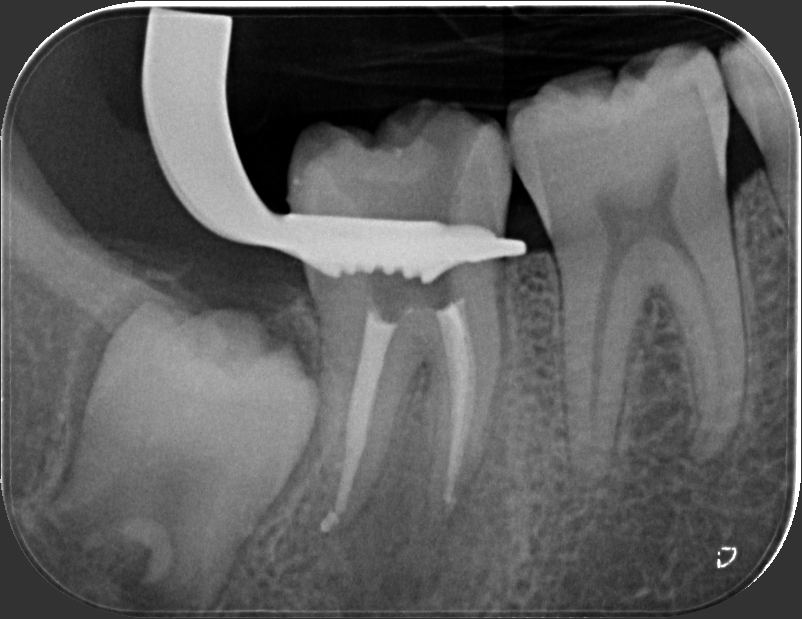

Caso clinico – trattamento ortogrado di 2° molare inferiore